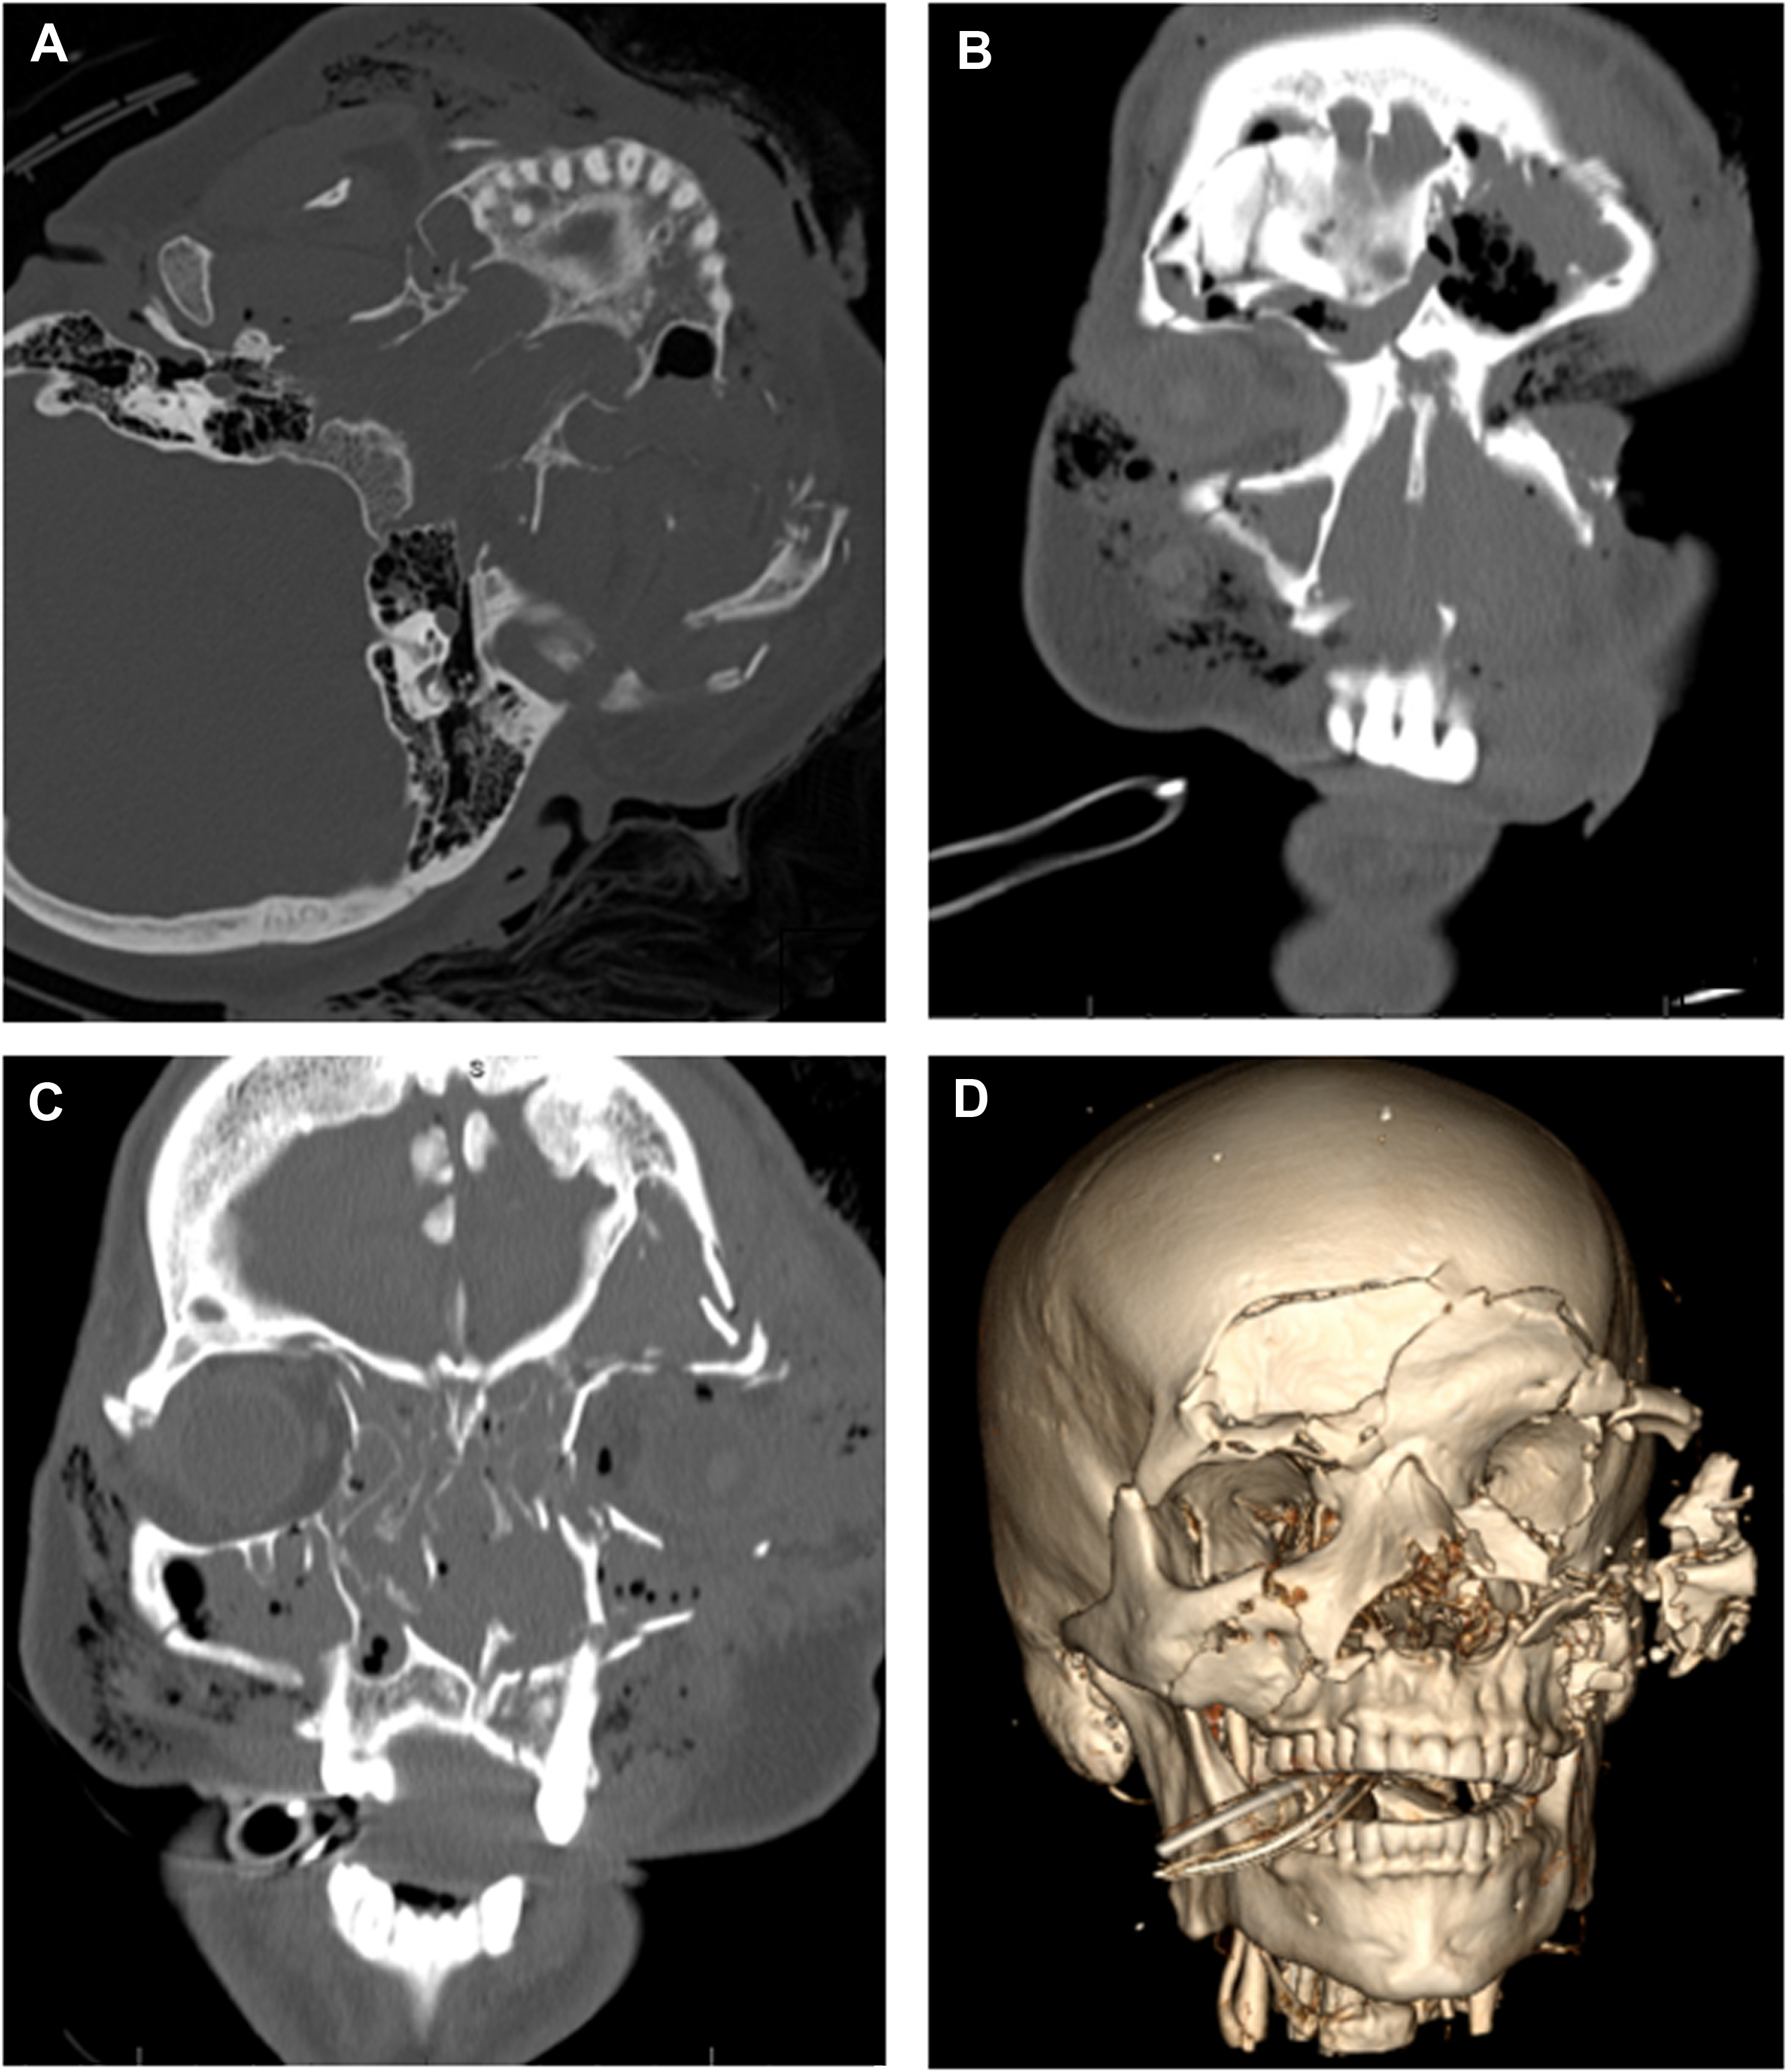

The excellent resolution of CT and the availability of three-dimensional (3D) reconstruction have made CT scanning the method of choice for evaluating complex facial fractures. With current technology, fine-cut CT is a largely preferred modality as this will provide detail necessary to fully visualize the complexity of the trauma and provide enough data to use 3D imaging and 3D printing technology if desired. The ideal resolution is <0.1 mm which can be achieved by modern cone beam computed tomography imaging; hospital CTs should routinely be able to provide <1 mm slices which is acceptable. Vertical and horizontal structures are viewed best on axial and coronal views, respectively. A methodical and thorough evaluation is important in order to accurately diagnose midface fractures. MRI may be used to evaluate soft tissue, intracranial, and vascular injuries, but it has limited usefulness in evaluating skeletal injuries. Imaging of the brain and cervical spine and neck vessels should be performed to evaluate for BCVI with CTA. This is critical for severe injuries or when involvement of vessels is suspected.

There are many challenges when it comes to repairing Le Fort level facial trauma. First, there is the complexity of facial anatomy and importance of restoring function and structure to the facial skeleton with the primary goals being to restore occlusion and obtain bony union which will facilitate proper mastication and speech and minimize pain. Visualizing 3D relationships from a two-dimensional image is a challenge, especially in regions with complex 3D anatomy. It can be difficult to directly view the deep facial skeleton from esthetic incision lines, and it can therefore be difficult to visually assess the intraoperative result for ideal projection and position. Additionally, edema limits evaluation of symmetry. Use of preoperative and intraoperative imaging can help address some of these challenges. With the availability of intraoral scanners, 3D images of the teeth can be obtained and fused with CT imaging. This surface-generated image is not distorted by dental materials like images obtained using ionizing radiation. This allows for more accurate representation of the dentition and occlusion and permits accurate fabrication of planned surgical splints that can recreate a planned occlusion intraoperatively. Image-guided simulation with use of 3D CT allows for preoperative analysis and manipulation of images as part of a comprehensive surgical planning session. Surgeons can then manipulate the fractured segments while observing the effect on reference anatomic structures, compare the fractures to “standard anatomy” or unaffected sides, and create micromovements which are easily reproducible in vivo. Although 3D reconstruction of scans can provide an important tool for the operative surgeon, it is critical that the images be evaluated carefully in the nonreformatted views. Volume averaging in the 3D reconstruction can underestimate fractures and may mislead a surgical team. Nevertheless, surgeons report a subjective preference for viewing images in 3D, and one study shows improved diagnostic accuracy with 3D CT scans.